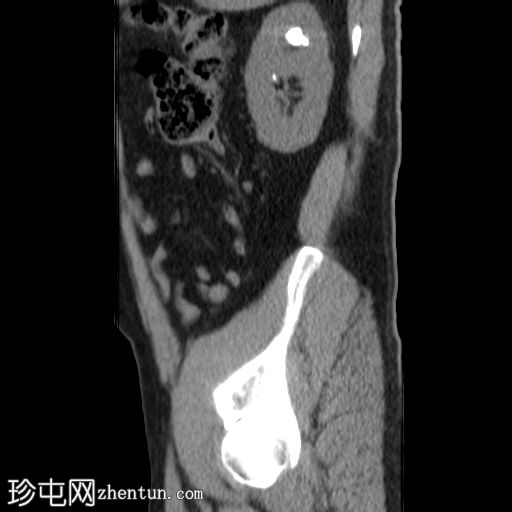

矢状位(非增强)

右肾上盏内可见一中等大小的结石,大小约为16 x 13 x 15 mm。右肾中盏内可见一小结石,大小约为4 x 2 mm。右肾下盏内可见另一小结石(过小无法测量)。未见肾盂肾盏扩张。

非增强 CT KUB 显示右肾多发结石,其中上肾盏结石较大,大小为 16 x 13 x 15 mm,密度较高(平均约 1060 HU),符合钙结石的特征。中肾盏和下肾盏可见其他较小的结石。

肾盂肾盏系统未见扩张,提示无梗阻性病变。该发现与患者反复腰痛的病史相符,腰痛可能与结石移位有关,而非当前存在梗阻。